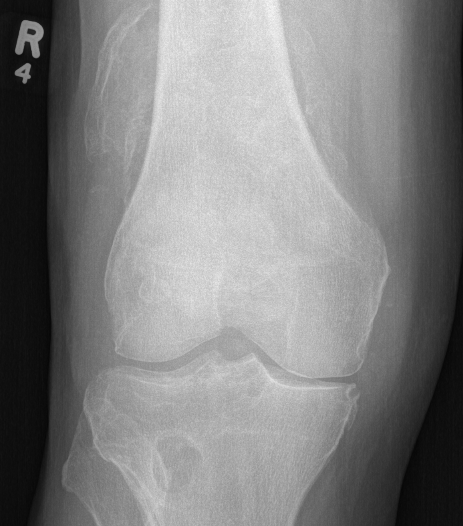

X-ray

Demonstrate calcified lesions / synovial osteochondromatosis